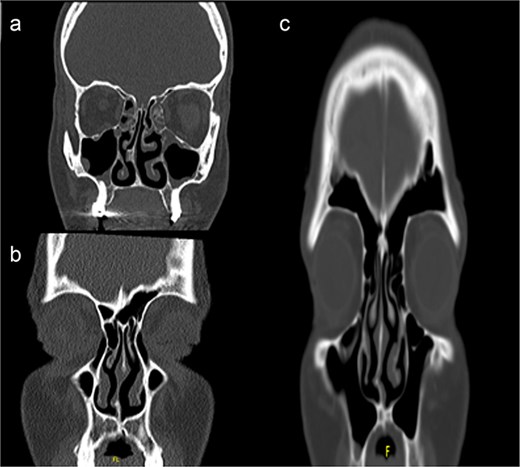

Unlike traditional techniques that require extensive septal exposure using kilian or hemitransfixasion incisions, our INES approach utilizes a targeted horizontal incision directly over the deviated from posterior to anterior (Fig. 3). Through this focused incision, superior and inferior mucosal flaps are carefully elevated, limiting the dissection to the deviated area only. This conservative approach maintains the integrity of the contralateral mucoperichondrium and preserves the surrounding normal septal architecture.

Stepwise illustration of the INES technique. (a) Deviated segment identification; (b) limited mucosal incision and flap elevation; (c) targeted resection of deviated cartilage; (d) mucosal closure without using Silastic sheets/suturing.

Under direct endoscopic visualization, the deviated cartilage and/or bone is precisely identified and resected. This focused correction allows for removal of only the pathological segment while maintaining the structural support of the remaining septum. Meticulous hemostasis is maintained throughout the procedure to ensure optimal visualization and surgical precision (Video 1).

Upon completion of the septal correction, the mucosal flaps are reapproximated. One of the distinctive features of this technique is that routine sialstic sheths are typically not required in most of the patients, although quilting sutures may be placed if deemed necessary based on individual case requirements.